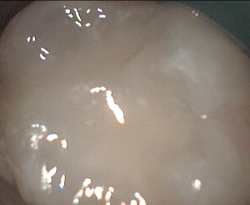

very groovy permanent molar + mild decay Restored